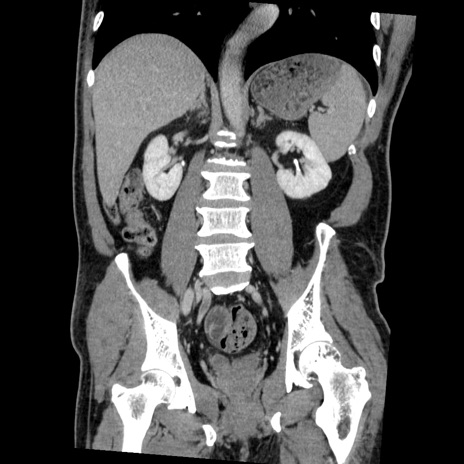

症例22(冠状断像)

【症例】50歳代男性

【主訴】腹痛

【現病歴】AVMからの被殻出血のため回復期リハ病棟入院中。 本日午後3時頃急に下腹部痛が出現した。

【既往歴】AVM、被殻出血、虫垂炎、高血圧

【身体所見】意識晴明、左半身不全麻痺、会話の理解は良好、36.5°C、腹部:膨隆、全体に板状硬、下腹部正中に圧痛点あり、反跳痛-、筋性防御不明、右下腹部にope scar

【データ】WBC 9400、CRP 0.06